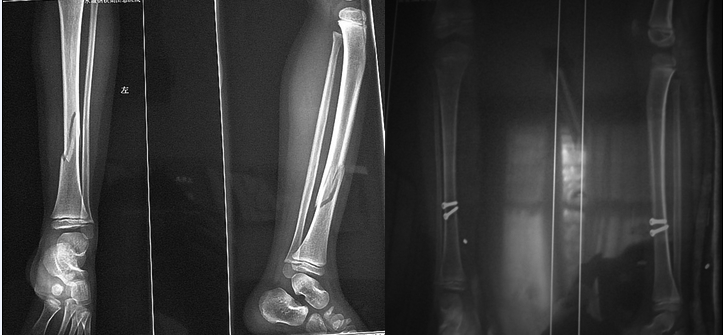

有限切开内固定结合外固定治疗儿童胫骨骨折

胫骨骨折术后骨髓炎治愈病例_钱红波

健康咨询描述:小腿胫骨下三分之一你好,你说小孩胫骨下1/3骨折。这个位置的骨折恢复得较慢。但是由于宝宝

需要注意的是如果胫骨骨折累及到骨骺、生长点需要特殊的处理方式,而且胫骨的皮质骨和松质骨的愈合时间也有

小孩左胫骨下段骨折要多久愈合?孩子的情况是因为外伤以后造成了胫骨骨折,现在已经有骨痂了,说明愈合的

你说的这种情况成人胫骨骨折可能你好,临床治疗胫腓骨骨折需要8-12周的恢复时间,期间注意尽量不要着急用患

但一般情况下,胫骨骨折要打石膏三个月.应为级胫骨是如果是胫骨中下1/3骨折,一般也是骨折愈合的比较慢的.

儿童胫骨骨折的愈合时间随着年龄增大逐渐增长,具体还与个人的营养状况有关。通常情况下,2岁以下包括婴

骨折、胫腓骨双根据临床观察,不同的部位,不同的年龄,骨折 愈合时间有差别,年龄越小 骨折 愈合越快,